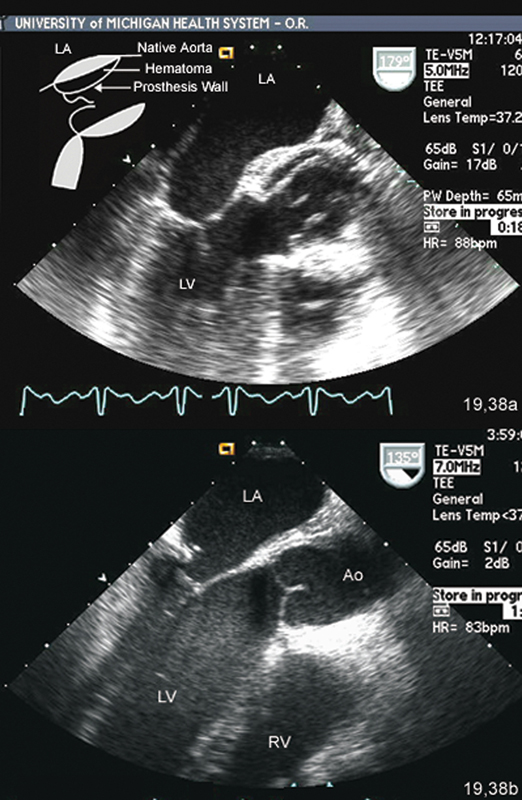

فحوصات تشخيصية لبعض امراض القلب والشرايين التاجية